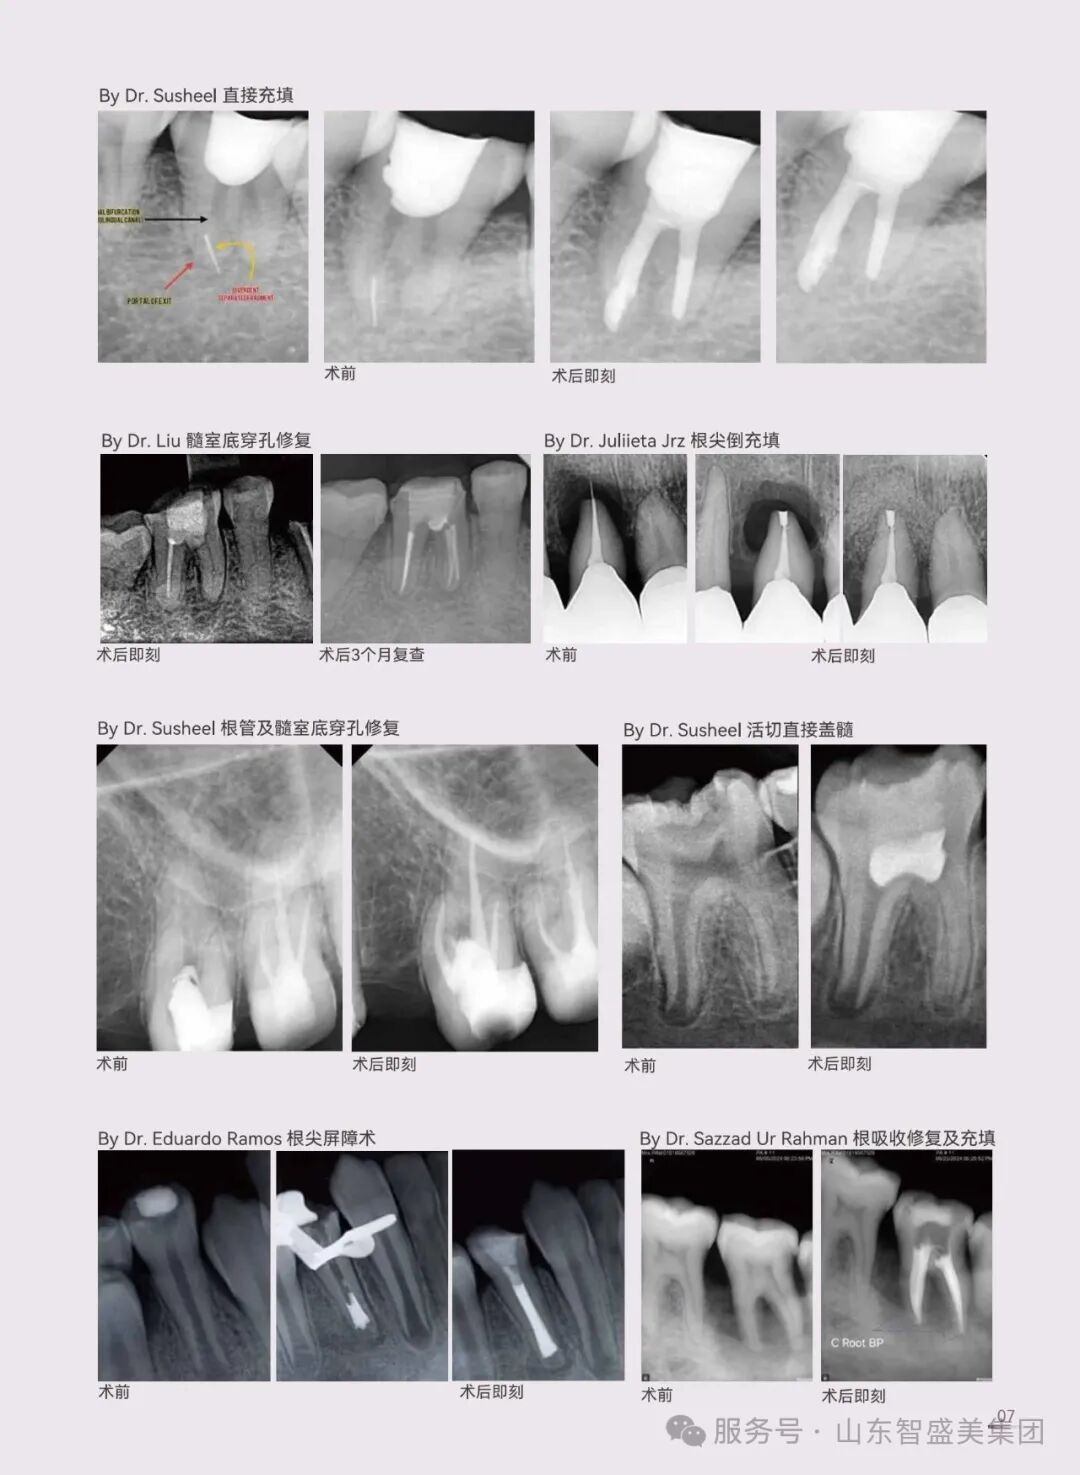

不管是间接盖髓、直接盖髓,还是活髓切断、髓室底穿孔修复,乃至侧穿修补、牙根内吸收、根尖倒充填、根尖屏障术、血运重建等情况,C-Root BP 都能 “大显身手” ,覆盖多种根管治疗场景,成为口腔医生诊疗工具箱里的 “万能钥匙” 。

看看这些临床案例: